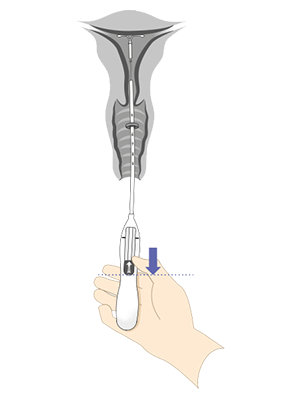

Énhånds innføring med Bayer-innføringssystem

Det integrerte innføringssystemet gjør det mulig for deg som lege, jordmor eller helsesykepleier å klargjøre innlegget med én hånd. Innføringshylsens diameter er 3,8 mm

Kyleena er allerede forhåndslastet i riktig horisontal stilling for innføring

Trådene er låst i innføringssystemets håndtak for å unngå utilsiktet vikling

Innføringssystemet har ergonomisk formet glideknapp og håndtak

8 trinn for riktig plassering av Kyleena